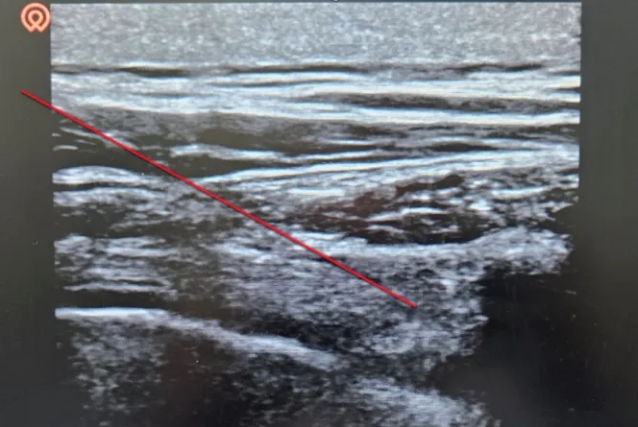

图为超声引导下椎旁间隙注射,红线为穿刺路径